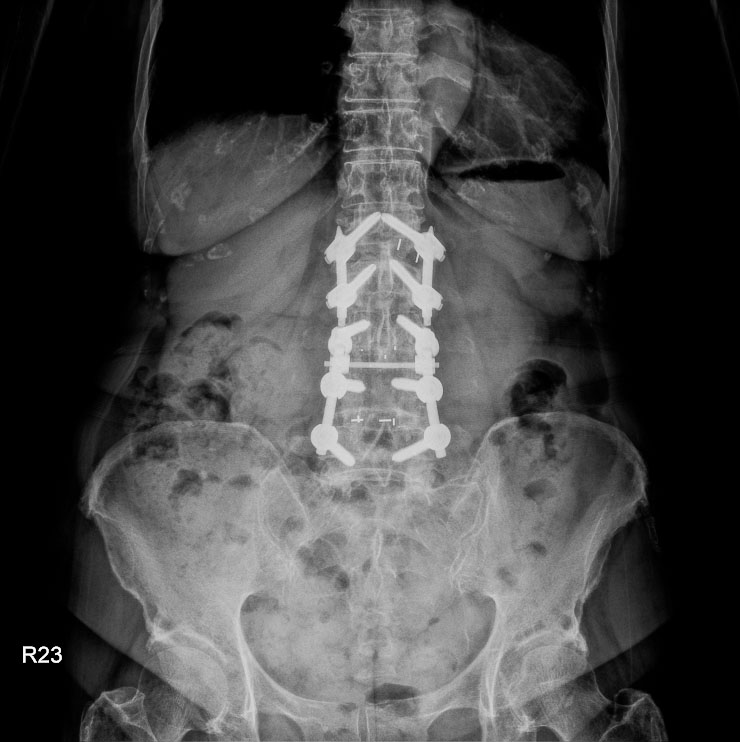

十七歲的何同學在國中時期便被父母注意到體態問題,確診為脊椎側彎。當時因角度尚未惡化,家人僅持續追蹤觀察。但隨著成長,側彎角度逐漸加重,影響了少女最在意的身形外觀,何同學及父母跟醫師討論評估後,醫師建議進行矯正手術。台中慈濟醫院神經醫學中心主任林英超表示,青少年的長節脊椎側彎矯正一直被視為高難度手術,不僅手術時間長,也可能伴隨出血量大與神經損傷風險。因此,神經醫學中心團隊安排在「複合式手術室」進行手術。

醫療團隊在何同學的手術中,運用三維立體導航系統與複合手術室影像設備,即時建立脊椎三維影像。醫師可以在螢幕上清楚看到每一節椎骨與椎弓根的角度,並計算最佳螺釘植入路徑。透過導航系統輔助,鈦合金骨釘的置放精準度提升到接近百分之百,大幅降低神經傷害與植體偏移風險。

台中慈濟醫院神經醫學中心於複合式手術室成功完成脊椎側彎矯正,術後復原速度較傳統快速許多。